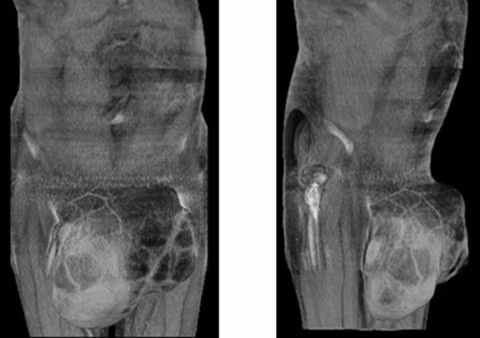

| Từ một chấm nhỏ, khối u trở nên to bất thường chỉ sau 12 tháng. |

Chỉ sau 12 tháng, khối u phát triển nhanh chóng. Đến khi nó có kích cỡ tương đương như một trái bóng thì Bod mới tiến hành chụp chiếu kiểm tra.